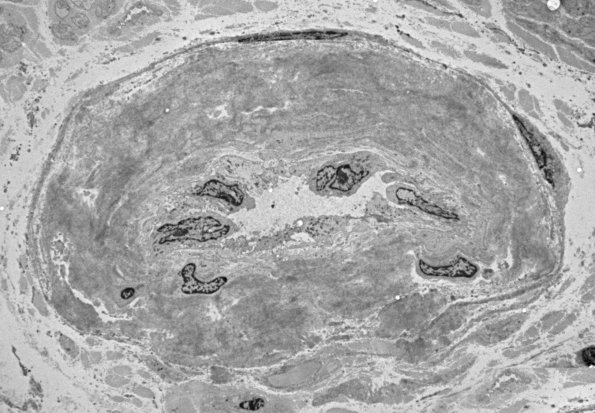

1G3-6 This endoneurial venule has an expanded wall which consists of aggregates of fibrils. (electron micrographs)